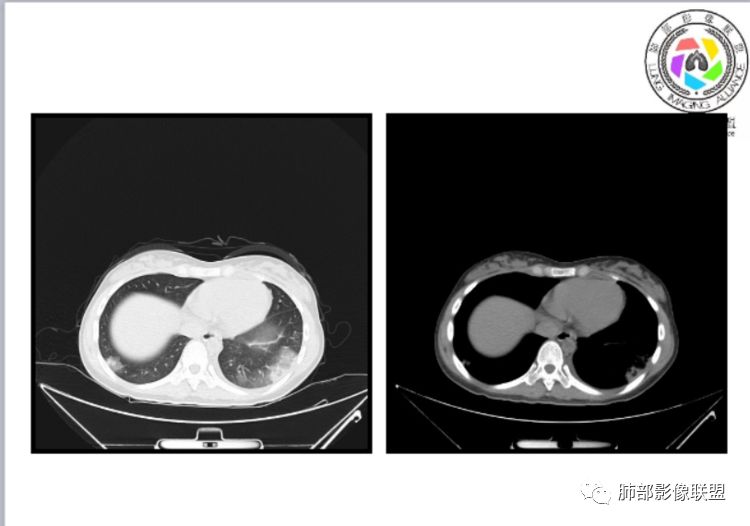

小微:右肺下叶斑片状密度增高影,抗炎治疗6天后复查,双肺下叶出现斑片状密度增高影,排除炎性病变,D2聚体特别高,考虑肺栓塞,肺梗死,建议增强扫描。王开金江津中心医院呼吸科:@岳微-辽宁PLA234医院放射科?支持,患者年轻女性,胸痛主诉,使用雌激素,高危人群,心率快,d二聚体升高,右下叶斑片加肺动脉明显增宽,抗感染无效,要考虑PTE,建议肺动脉ctpa。傅昌瑜:19岁,女性,右侧胸痛2天,发热以中度热为主,D—二聚体升高,肺动脉主干增宽,病灶位于胸膜下,抗感染后增多,近来有服用炔雌醇环丙孕酮片2周期史,诊断:肺栓塞,下一步完善肺CTPA检查。阿仙奴:青年女性,急性起病,胸痛入院,月经不调史,目前服用孕酮片。流感抗体阳性,d二聚体升高,无低氧血症。右肺下叶基底段胸膜下磨玻璃样改变,肺动脉增宽,治疗过程出现发热,复查左下叶胸膜下新发病灶。考虑:肺栓塞(服用孕酮相关)?奔跑的37°Doctor(陆喜红 ) :年轻女性,胸痛 急性病程,有服用雌激素避孕药史(是否有血液循环的改变,高凝状态),实验室D二聚体很高(也是提示血液高凝状态) ,第一次CT,右下肺胸膜下斑片状密度增高模糊影,肺动脉形态密度未见明显异常,抗炎后复查,肺动脉干及其分支,感觉增粗了一点,局部形态有点饱满,双下肺胸膜下片状影增多,锁定肺动脉栓塞应该不会错,建议CTA检查飞鹰行动:青年人,女性,右肺下叶斑片状密度增高影,抗炎治疗6天后复查无好转,,双肺下叶出现斑片磨玻璃影,主肺动脉增粗,结合患者服用的药物和D2聚体特别高,考虑肺栓塞,建议CTA。李:口服避孕药,有危险因素,肺动脉较主动脉增宽,D二聚体增高,胸膜下片状影,考虑肺栓塞;@晨义工张帅,医附属潞河医院呼吸?是否痰中带血很关键,不知有没有张帅:患者入院后第七天出现痰中带血风之子:病程中有发热,D—二聚体升高,肺动脉主干增宽,病灶分布于胸膜下,抗感染后增多,结合服药史诊断:肺栓塞,建议CTPA检查。不支持的地方是没有低氧血症,不明白为什么第二次复查ct双侧乳腺不对称,按理乳腺炎多见于哺乳期张帅:大家方向都在考虑肺栓塞:我提问两个问题:1 周围毛玻璃怎么回事?2左下肺小叶间隔增宽怎么回事?笨丫头:周围的磨玻璃应该考虑是肺梗死后出血渗出,同时合并机化性炎症小叶间隔增宽,我考虑应该是梗死后炎性渗出wonderful:我不支持肺栓塞 不能解释发热原因

张帅:好多老师都在说肺动脉增宽。肺动脉增宽标准是多少?程磊:29。或者比同层主动脉比值大于等于1

张帅:我量的虽然不标准,但不到24

CT平扫及间接征象:

1、一个或多个胸膜下斑片高密度影(梗死、出血、肺不张、肺水肿、炎性渗出),典型为胸膜下楔形影 ,尖端指向肺门

2、肺动脉高压(中心肺动脉扩张),有时可见肺动脉区高密度影。

3、肺血减少

4、马赛克灌注

5、膈肌升高、胸腔积液、心包积液